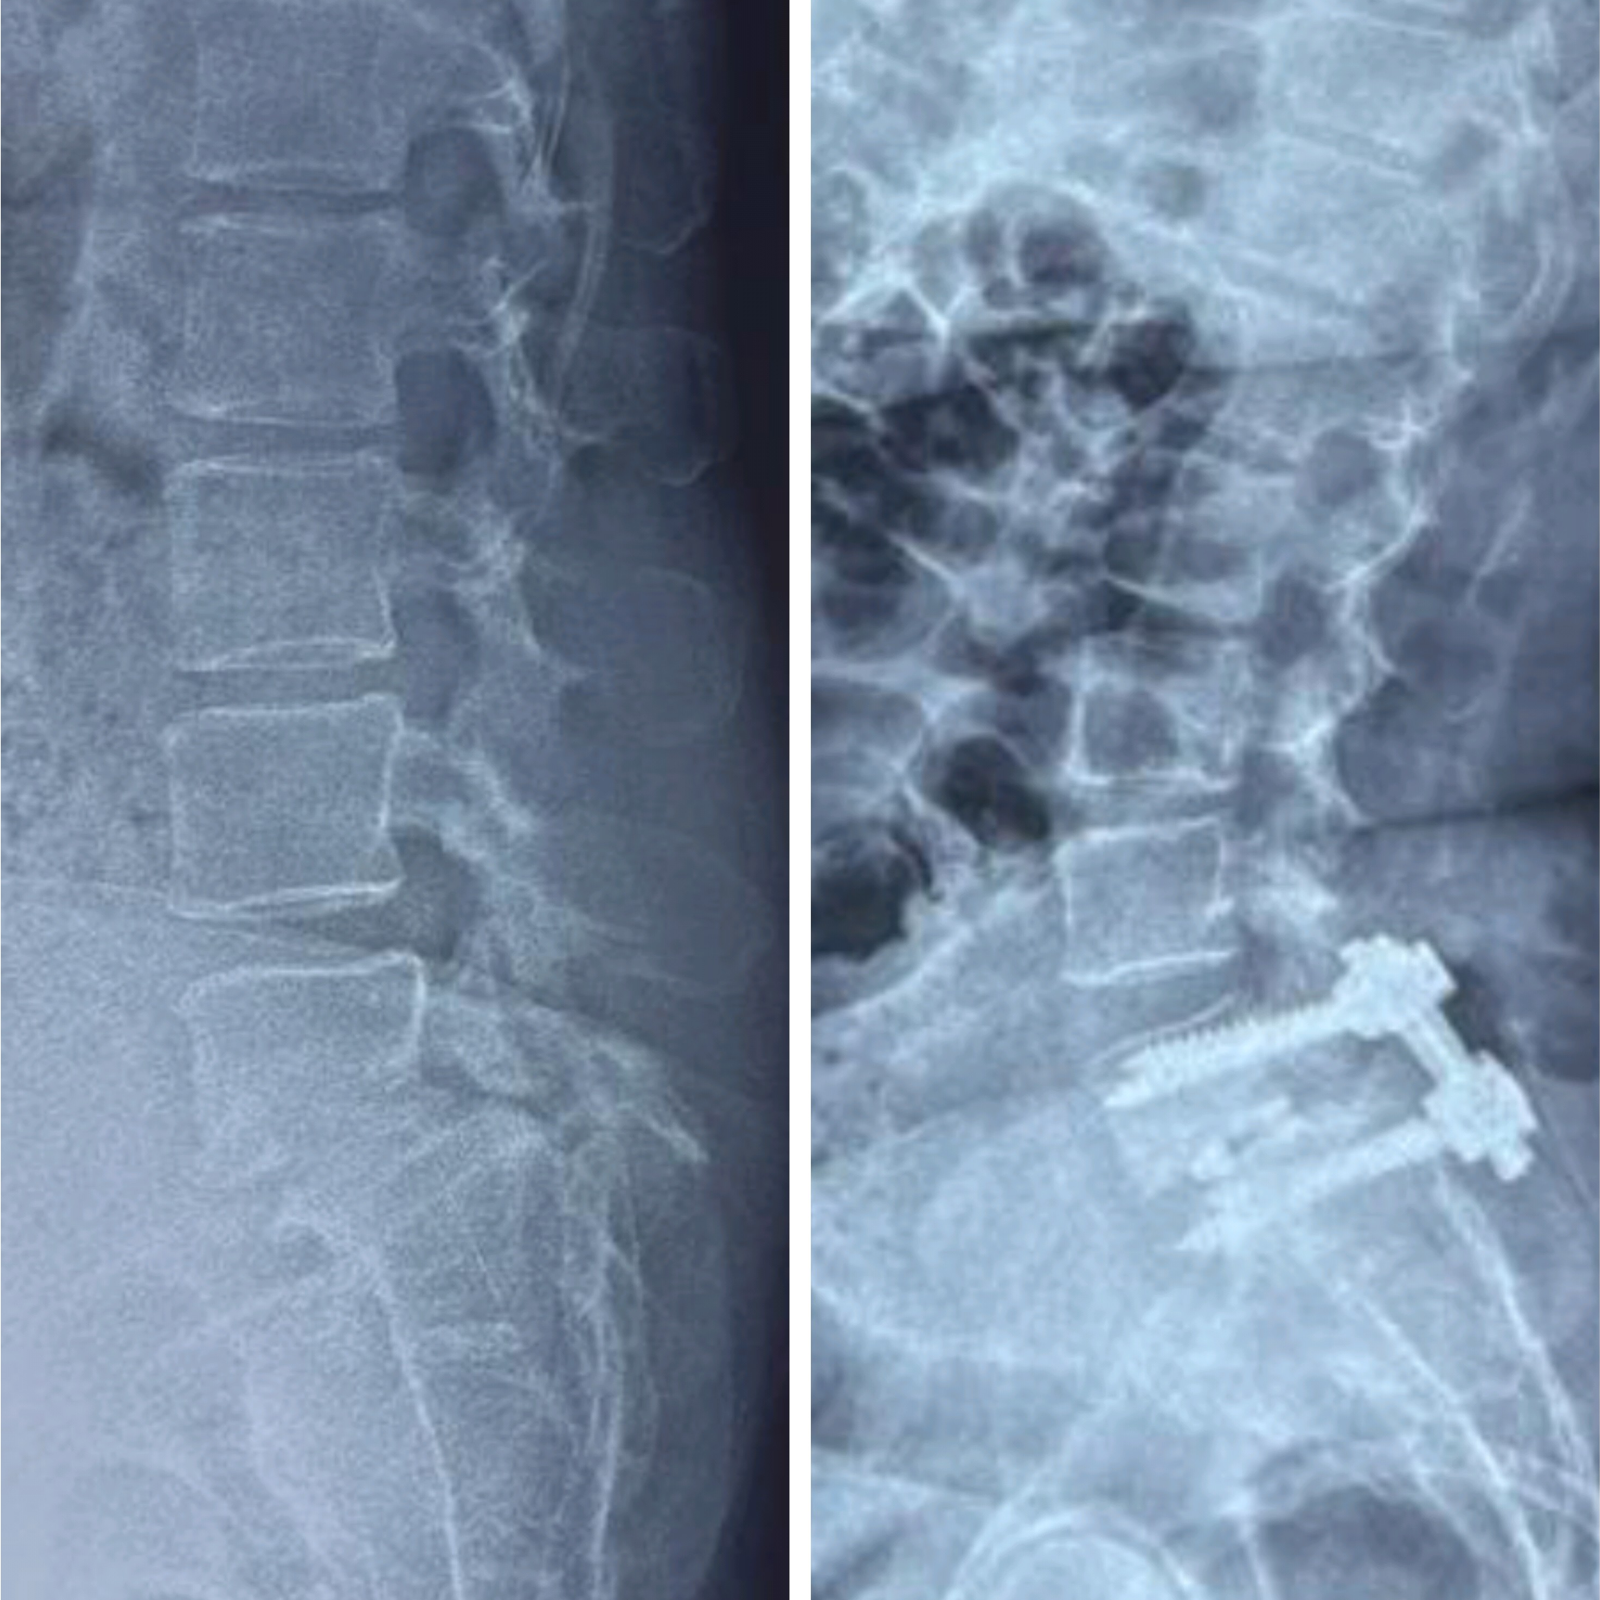

TLIF surgery for L5S1 Lumbar Spondylolisthesis #slipdisc #spinesurgery #spondylolisthesis